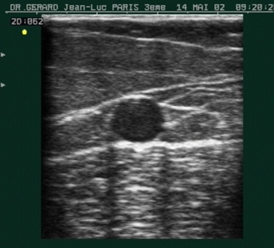

- Siêu âm Doppler đo tốc độ dòng máu và xem xét cấu trúc các tĩnh mạch chân, đánh giá tình trạng và mức độ suy giãn của các tĩnh mạch. Đây là xét nghiệm đơn giản, thuận tiện, dễ thực hiện và có độ chính xác cao.